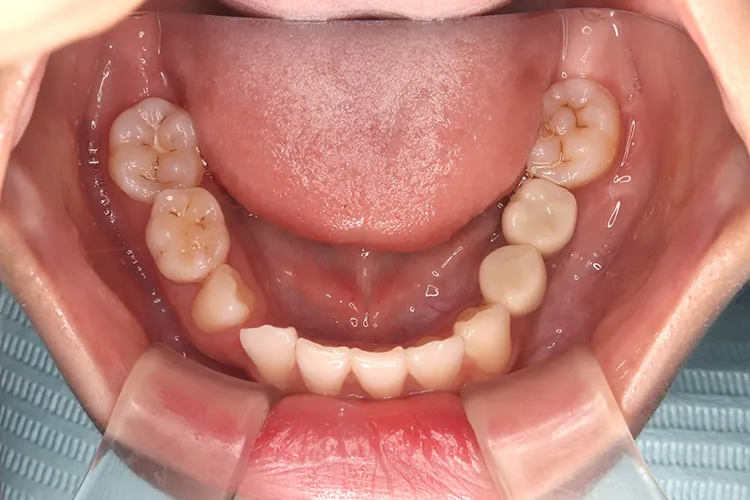

左下の大臼歯の欠損を長期間放置したために上の歯が下がってきてしまい、他の歯医者で被せを入れることができないと断られうちに来られました。下がってきてしまった上の奥歯を部分矯正で上に引っ張り上げ、下に被せ物を入れるスペースを作り、インプラントを入れて噛み合わせを回復しました。部分矯正開始から1年半で治療完了しました。

治療内容

左下67 欠損に対してインプラント治療を行った症例

部分床義歯を使用していたが、どうしても慣れない上にしっかり噛むことができないためインプラント治療を希望